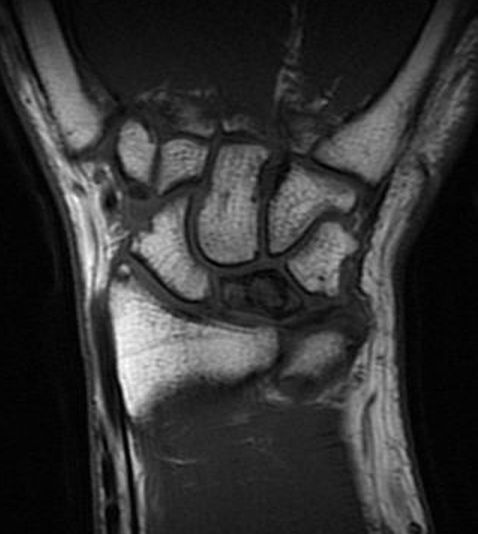

Stadium 2: Skleros av lunatum [1, 2]

Lunatummalaci stadium 2 med sklerotisk lunatum och ulnaminus